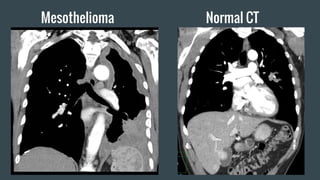

Mesothelioma Normal CT

Findings: Helpful in staging follow-up. Contrast-enhanced CT

used to assess tumor response to Chemotherapy. The calcified

pleural plaque indicates prior asbestosis exposure.

Impression: The lobulated pleural thickening in evident in the

right lung. Pleural effusion is minimal. Follow up pet scan to

confirm need for chemotherapy.